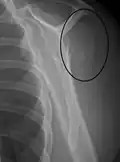

Fracture of the greater tuberosity of the humerus -

Multi-fragmented, or comminuted fracture of the proximal humerus with involvement of the greater tuberosity -